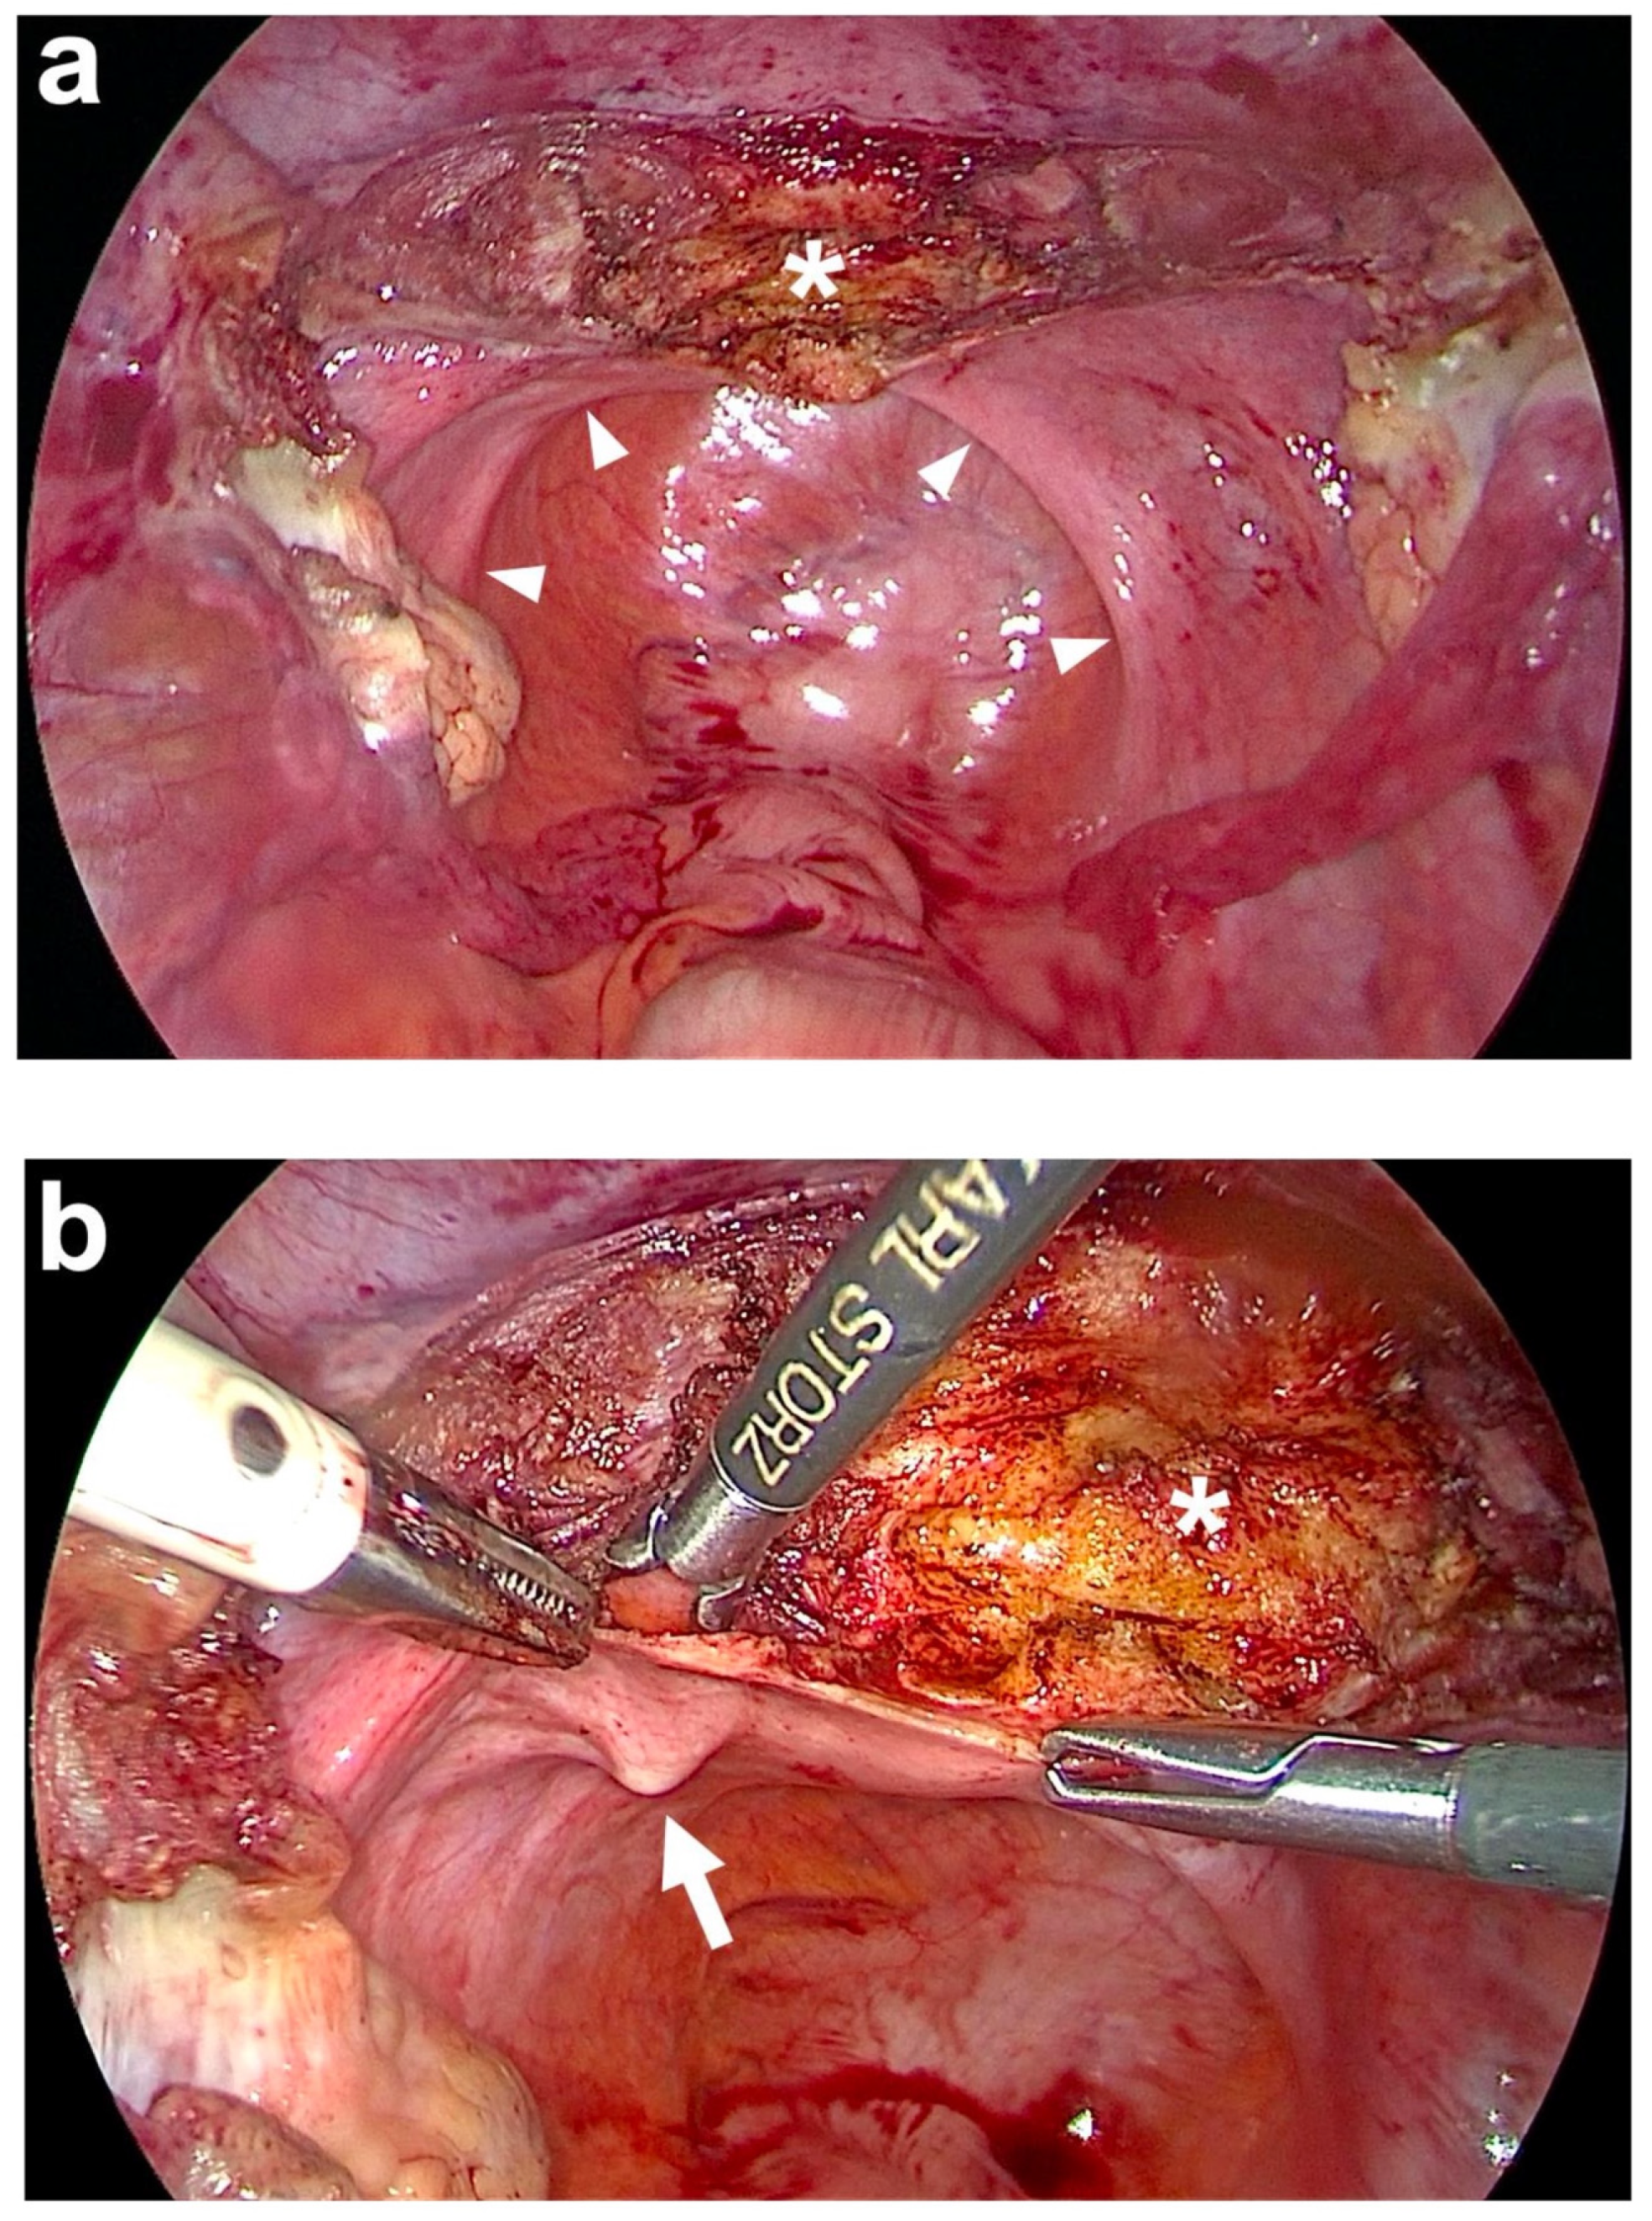

| Preparation of anterior fixation sides | Subtotal hysterectomy (if necessary) with monopolar electric knife above the origin of both USL and at peritoneal fold of bladder’s peritoneum at anterior cervix. | Subtotal hysterectomy (if necessary) with monopolar electric needle above the origin of both USL and at peritoneal fold of bladder’s peritoneum at anterior cervix (Figure 4a). |

| Preparation of posterior fixation sides | Incision of lateral peritoneum above S1/promontory for 2 cm on either side of rectosigmoid colon. | Incision of lateral peritoneum above S1/promontory for 2 cm on either side of rectosigmoid colon (Figure 5). |